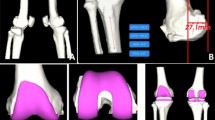

Restricted kinematically aligned TKA (rKA-TKA) is based on the concept of restricting the bone resection angle of the femur and/or tibia within the safe zone22,23,24. Recently, rKA-TKA for patients with severe preoperative HKAA has gained much interest, especially in Asian populations. The rKA-TKA can be performed within the MA-KTA-derived safe zone and is therefore a promising approach for patients with severe preoperative HKAA. A previous report showed that rKA-TKA could restore the kinematics of the native knee, prevent excessive coronal limb alignment, and provide the same or slightly better patient-reported outcome measures than MA-TKA without increasing the risk of midterm implant failure25. Nevertheless, rKA-TKA has some limitations with respect to the surgical approach. Computer-assisted surgical navigation is indispensable because it requires a precise bone resection angle14,26,27. Two previous studies estimated an additional cost of approximately 1,500–3,000 US dollar per patient when applying advanced techniques, compared with that when using the conventional TKA28,29. Thus, from the viewpoint of medical resources, it is difficult to perform rKA-TKA in any hospitals. To date, no study has shown the efficacy of rKA-TKA without computer-assisted surgical navigation for postoperative HKAA. Given that various rKA-TKA procedures may provide important information for surgeons and patients, we developed a manual rKA-TKA, which specializes in restricting the lateral tibial side, using a generic implant (Fig. 1, Vanguard ID; Zimmer Biomet, Warsaw, IN, USA). This implant is the only TKA design with two individual polyethylene bearings of different conformities on the medial and lateral sides. This enables surgeons to select bearings of different thicknesses and conformities personalized to patients.

Characteristic of Vanguard ID (CR implant). Thickness: Vanguard ID allows for changes in thickness independently. Every 1-mm difference in the bearing results in 1.2° of joint-line inclination (e.g., 9-mm medial bearing and 10-mm lateral bearing result in 1.2° of joint-line inclination). Constraints: Vanguard ID also allows for changes in conformity independently. Two types of bearing conformity exist—namely, the anterior stabilized (AS) bearing with high constrained design (tibia/femoral coronal conformity ratio: 1:1) and the bicruciate-preserving (XP) bearing with low constrained design (tibia/femoral coronal conformity ratio: 1.25:1). In all knees, an AS bearing is used on the medial side, whereas an XP bearing is used on the lateral side. AS anterior stabilized, XP bicruciate-preserving, CR cruciate-retaining.

Implant characteristics

Vanguard ID is the unique implant capable of individually customizing the medial and lateral polyethylene bearings through differential thickness and constraints (Fig. 1).

Thickness

Vanguard ID allows for changes in thickness independently. Every 1-mm difference in the bearing results in 1.2° of joint-line inclination.

Constraints

Vanguard ID also allows for changes in conformity independently. Two types of bearing conformity exist—namely, the anterior stabilized (AS) bearing with high constrained design and the bicruciate-preserving (XP) bearing with low constrained design. In this study, an AS bearing was used on the medial side, whereas an XP bearing was utilized on the lateral side.